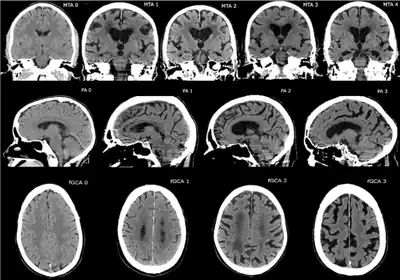

Brain CT with different grading systems of cerebral atrophy (seen as decreased size of gyri and secondary increased size of sulci):[19]

- Medial temporal lobe atrophy (MTA)

- Posterior atrophy (PA)

- Frontal cortical atrophy (fGCA)

CT and MRI are most commonly used to observe the brain for cerebral atrophy. A CT scan takes cross sectional images of the brain using X-rays, while an MRI uses a magnetic field. With both measures, multiple images can be compared to see if there is a loss in brain volume over time.[20]